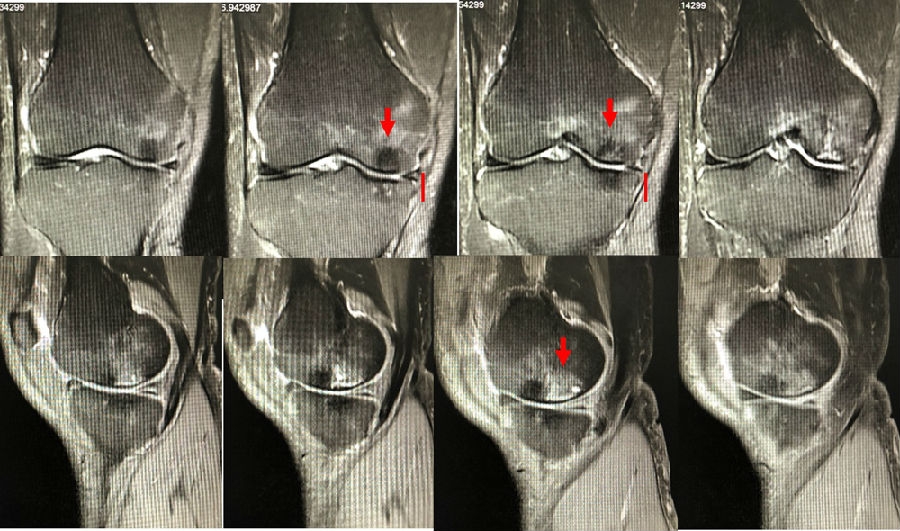

病例:女,65岁,主诉左膝关节内侧疼痛2月余。2017年11月X光未见左膝骨质异常。MR见股骨内侧髁骨坏死,半月板相对突出百分比(RPE)28.3%,合并内侧半月板后根部撕裂,矢状位病变区域前后径为11.67mm,关节线会聚角2.68°

予消炎止痛药物口服、静滴唑来膦酸钠注射液,避免负重6周,后改部分负重,12周后全负重。

2018年2月复查MR见骨髓水肿明显吸收,坏死灶边界清晰,半月板相对突出百分比(RPE)28.92%

2018年6月复查MR见骨髓水肿基本完全吸收,坏死区修复良好,半月板相对突出百分比(RPE)38.54%,患者临床症状消失。

提示坏死好转了,但半月板突出进展了,膝关节的退变加重了。

病例1:女,65岁,主诉右膝关节内侧疼痛1周。2018年1月X光未见右膝骨质异常,MR检查见股骨内侧髁骨坏死,半月板相对突出百分比(RPE)28.99%,关节线会聚角1.4°。

予切开行克氏针钻孔减压,口服消炎止痛药物、钙剂及骨化三醇,不负重6周,后改部分负重至3个月。2018年4月复查MR见骨髓水肿基本完全吸收,坏死区局限并修复良好,半月板相对突出百分比(RPE)32.08%,患者临床症状消失。

病例2:女,69岁,主诉左膝关节内侧疼痛1月余。2017年11月X光见右膝股骨髁负重区的软骨下区域出现了椭圆形透亮影,MR检查见股骨内侧髁骨坏死,合并内侧半月板外突和后角层裂,半月板相对突出百分比(RPE)25.32%,矢状位病变区域前后径为23.96mm,关节线会聚角6°。

予克氏针钻减压,消炎止痛药物口服、静滴唑来膦酸钠注射液,避免负重6周,后改部分负重至3个月,患者依从性差。2018年1月复查MR见骨髓水肿少许吸收,坏死区扩大,半月板相对突出百分比(RPE)33.53%,矢状位病变区域前后径为26.89mm,患者仍有膝关节疼痛症状,建议行手术治疗,患者拒绝手术后失访。

病例3:男,70岁,主诉右膝关节疼痛1年余。查体右膝无肿胀畸形,膝活动度0-120°,内侧间隙压痛。

已经累及44%的股骨内侧髁病变,半月板轻度突出,内侧后角水平撕裂

MRI上深度>20mm

治疗选择保守还是手术?

保守治疗4个月后复查

保守治疗后效果欠佳,坏死范围扩大、塌陷